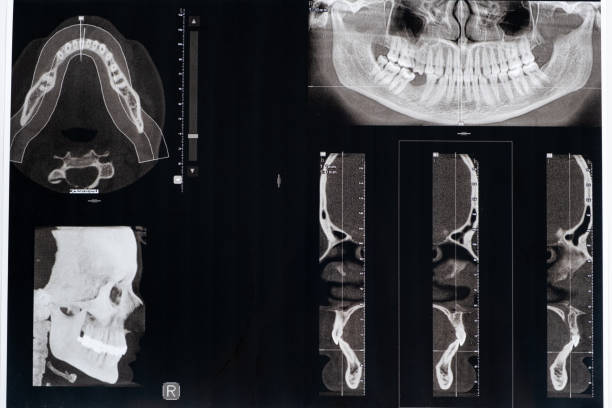

턱관절 통증 확인하는 방법

턱관절 장애를 확인하려면 몇 가지 간단한 테스트를 진행할 수 있습니다.

- 손가락 테스트: 입을 크게 벌리고 손가락 세 손가락을 입 안으로 넣어보세요. 턱관절 장애가 있는 경우 어려움을 겪을 수 있습니다.

- 대화 테스트: 입을 크게 벌리고 대화를 10번 반복해보세요. 턱관절 장애가 있는 경우 입을 벌릴 때 소리가 나거나 아프게 느껴질 수 있습니다.

- 물리적 테스트: 턱을 아래로 내려 어금니를 가지런히 만지며 아프거나 이상한 소리가 나는지 확인해보세요.

- 입 벌림 테스트: 입을 크게 벌리고 어금니를 최대한 멀리 이동시켜보세요. 이때 아프거나 어려움을 겪는다면 턱관절 장애가 있을 수 있습니다.